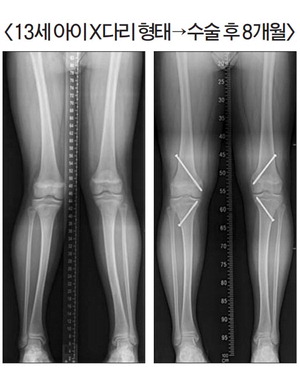

| ¾î¸°ÀÌÀÇ ´Ù¸® ¸ð¾çÀÌ XÀÚ ¶Ç´Â OÀÚ ÇüÅ¿¡ ´ëÇÑ ±³Á¤Àº º¯È ÃßÀ̸¦ °üÂûÇß´Ù°¡ ¼ºÀåÆÇÀÌ ´ÝÈ÷±â 1~2³â Àü¿¡ ¼ö¼úÀû Ä¡·á¸¦ °í·ÁÇÒ ¼ö ÀÖ´Ù. ºÎ»êÀÇ·á¿ø Á¤Çü¿Ü°ú ¼ÇѾó(Àü¹®ÀÇ) °úÀåÀÌ ¾î¸°ÀÌ È¯ÀÚÀÇ ´Ù¸® »óŸ¦ »ìÆìº¸°í ÀÖ´Ù. |

¼ºÀÎÀÇ OÀÚ XÀÚ ´Ù¸® ¼ö¼úÀº Àý°ñ¼úÀ» ½ÃÇàÇÏÁö¸¸, ¾î¸°ÀÌ´Â ¹«¸°üÀýÀ» ÀÌ·ç´Â ´ëÅð°ñ°ú °æ°ñÀÇ ³»¡¤¿ÜÃø ¼ºÀåÆÇ Á¶Àý·Î ±³Á¤ÇÒ ¼ö ÀÖ´Ù. ±×°Í¿¡´Â ¿©·¯ ¹æ¹ýÀÌ Àִµ¥, ÃÖ±Ù¿¡´Â 1cm Á¤µµ ÀÛ°Ô Àý°³ÇÑ µÚ ³ª»ç¸øÀ¸·Î ¼ºÀåÆÇ ÀϺθ¦ ¾ïÁ¦ÇØ °¢±³Á¤À» ÇÑ ´ÙÀ½, °°Àº Àý°³·Î ³ª»ç¸øÀ» Á¦°ÅÇÏ´Â ¹æ½ÄÀÌ ¸¹ÀÌ ÀÌ·ïÁø´Ù. ÀÌ´Â ¼ö¼ú ÈÄ ¹Ù·Î ÀÏ»ó »ýȰÀÌ °¡´ÉÇϸç, ´ëü·Î 1³â ³» ±³Á¤ÀÌ ³¡³´Ù. ´Ù¸¸, ³ª»ç¸øÀ» Á¦°ÅÇÑ ÈÄ ³²Àº ¼ºÀåÆÇÀÇ ¿µÇâÀ¸·Î ÀÎÇØ º¯ÇüÀÌ Àç¹ßµÉ ¼ö ÀÖ´Ù. µû¶ó¼ ¼ºÀåÀÌ ¸¶¹«¸®µÆÀ» ¶§ ³ª»ç¸øÀ» Á¦°ÅÇÒ ¼ö ÀÖµµ·Ï ÀûÀýÇÑ ³ªÀÌ¿¡ ¼ö¼úÀ» ÇØ¾ß ÇÑ´Ù. º¸Åë ¼ºÀåÆÇÀÌ 1~2³â ³²¾ÒÀ» ¶§°¡ ÁÁ´Ù. ³²ÀÚ ¾ÆÀÌ´Â ÁßÇб³ 1Çгâ, ¿©ÀÚ ¾ÆÀÌ´Â Ãʰæ Á÷Èĸ¦ ±× ½Ã±â·Î º¼ ¼ö ÀÖ´Ù.

³ª»ç¸øÀ» ÀÌ¿ëÇÑ ÀϽÃÀû ¼ºÀå ¾ïÁ¦¼úÀº ¼ºÀå°ú ÇÔ²² ±³Á¤µÇ´Â ¿ø¸®¿©¼ ¹Ýµå½Ã ¼ºÀåÆÇÀÌ ³²¾Æ ÀÖ´Â »óÅ¿¡¼ ½ÃÇàµÅ¾ß ÇÑ´Ù. ¿¹»óÄ¡ ¾Ê°Ô ۰¡ ´õµð°Ô ÀÚ¶ó¸é ±³Á¤¼Óµµ°¡ ´Ê¾îÁö°í, ±³Á¤ ¿Ï·á Àü¿¡ ¼ºÀåÀÌ ¸ØÃß¸é ±³Á¤ÀÌ ºÎÁ·ÇÑ »óÅ·Π¡®°¢º¯Çü¡¯ÀÌ ³²°Ô µÈ´Ù. ¶ÇÇÑ °¢±³Á¤ÀÌ ¿Ï·áµÈ µÚ ³ª»ç¸øÀ» Á¦°ÅÇÏ¸é ¼ºÀåÇÏ¸é¼ ´Ù½Ã ¿ø·¡ ¸ð¾çÀ¸·Î µ¹¾Æ°¡·Á´Â ¡®µÇµ¹ÀÌ Çö»ó¡¯ÀÌ ³ªÅ¸³¯ ¼ö ÀÖ´Ù. µû¶ó¼ ´ëºÎºÐÀº °¢±³Á¤À» ¾à°£ °ú±³Á¤ÇÑ µÚ Á¦°ÅÇϴµ¥, °ú±³Á¤ »óÅ¿¡¼ ¼ºÀåÀÌ ³¡³ª´Â °æ¿ìµµ »ý±æ ¼ö ÀÖ´Ù´Â °ÍÀÌ´Ù.